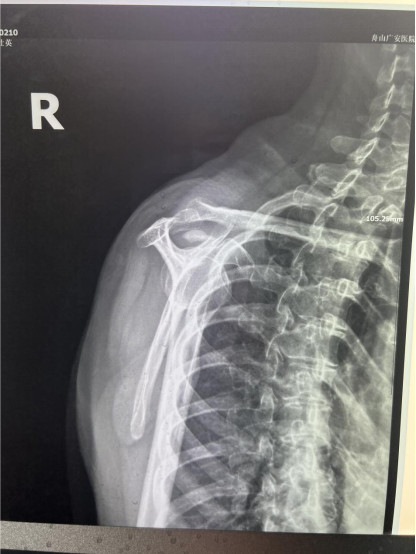

賀大媽慕名來廣安醫(yī)院找羅軍主任就診,面對羅醫(yī)生,賀大媽哭訴:“羅醫(yī)生,我真想剁下自己的這只胳膊。”羅軍主任根據(jù)患者的癥狀拍片,診斷為岡上肌鈣化性肌腱炎,隨后,羅醫(yī)生為李大媽進(jìn)行了肩關(guān)節(jié)鏡微創(chuàng)手術(shù),竟從她的右肩“擠”出“牙膏”。

是不是只要病人撐得住,讓鈣鹽吸收就沒事了?羅軍主任表示,經(jīng)保守治療無法緩解或病程長的患者,應(yīng)盡早采取手術(shù)治療。而且,部分患者鈣鹽無法完全吸收,拖下去只會使病情惡化,造成肩膀肩袖肌腱的損傷。

羅軍主任表示,很多人會把肩痛都?xì)w因于肩周炎,這是一個(gè)很大的誤區(qū)。其實(shí),肩痛人群中只有15%左右是肩周炎,大部分肩膀疼痛由于肩袖損傷、肩峰撞擊征、鈣化性肌腱炎。而大多數(shù)人也因此認(rèn)為忍一忍就會自愈,常常延誤治療,關(guān)節(jié)鏡微創(chuàng)治療鈣化性肌腱炎,可以快速緩解疼痛,同時(shí)可以修復(fù)肩袖損傷,清理肩膀骨刺。